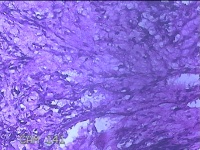

左大腿内侧包块

性别

男

年龄

21岁

临床诊断

脂肪瘤

一般病史

左大腿内侧起包块一月余。

标本名称

大体所见

灰白暗红色包块2.5x2x0.8cm一个,表面糜烂,切开包块呈实性,切面灰白暗红色,质软。

片子这个效果,没有胆量下诊断了。

脱水机的试剂多久没有更换了?